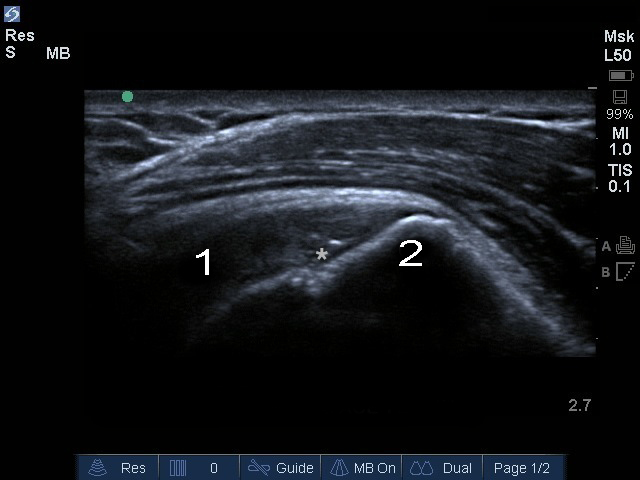

肩棘上筋皮質凹凸画像

スター:棘上筋関節表面断裂

棘上筋

大結節 (GT)